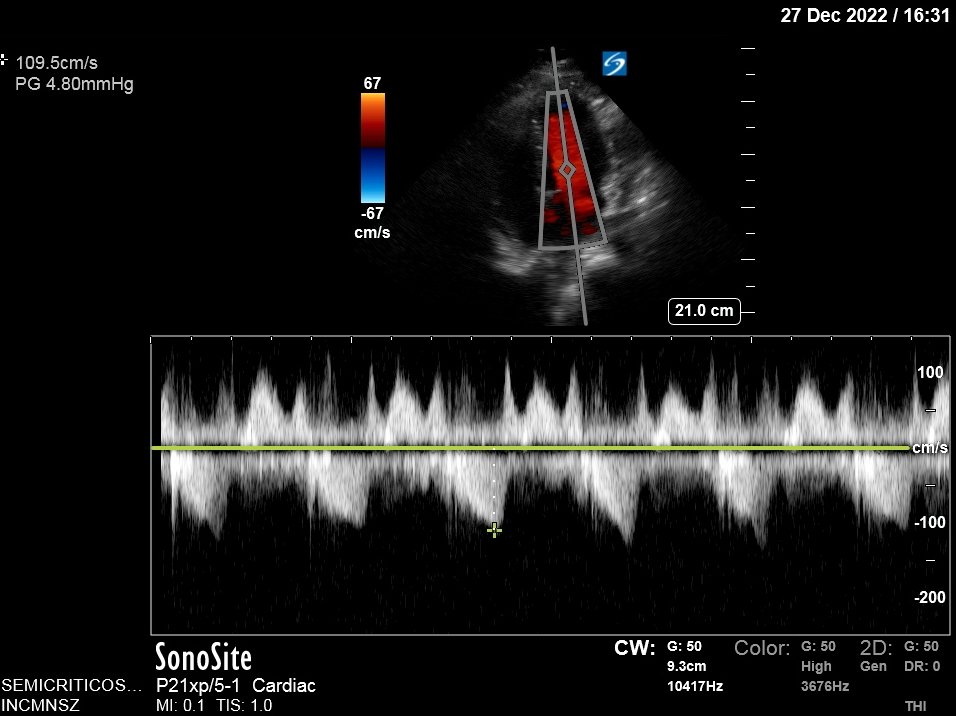

Fluid did help: BP now 105/69, gradient improved from 50 to 24 mmHg!

Gradient is now 4.8 mmHg (Not hemodynamically significant!)